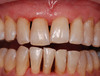

Cas 1: Parodontite

Le saignement gingival (ou gingivorragie) est un signe d’activité d’une maladie parodontale, en absence d’une fêlure/fracture. Un traitement parodontal non chirurgical permet de traiter la très majorité des cas.